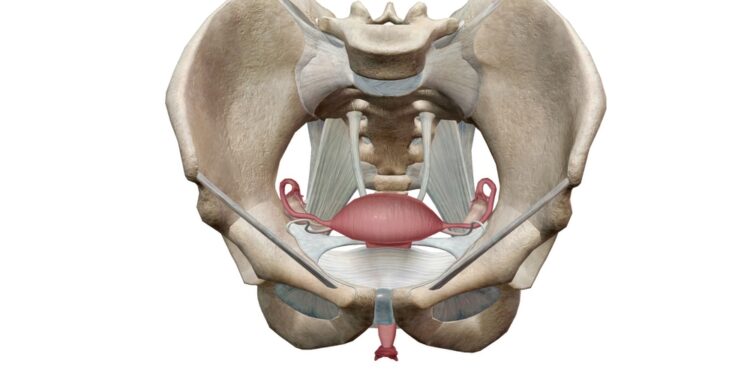

Levator ani sindromas – tai viena iš dubens dugno raumenų sutrikimų rūšių. Ši būklė atsiranda tuomet, kai dubens dugno raumuo, vadinamas levator ani, ima nevalingai spazmuoti ir susitraukia, o tai sukelia nemalonų skausmą ar nuolatinį tempimą ties tiesiąja žarna, tarpvietės srityje arba makštyje. Skirtingai nuo aštraus skausmo, dažnai jaučiamas duslus maudimas, kuris kartais gali pereiti į stipresnį, duriantį pojūtį.

Levator ani raumuo atlieka daug svarbių funkcijų: padeda išlaikyti dubens organus reikiamoje vietoje, atsakingas už tuštinimosi kontrolę. Nors levator ani sindromas nėra gyvybei pavojinga ar labai grėsminga būklė, jis gali smarkiai sutrikdyti kasdienę savijautą, jei nėra gydomas. Ši diagnozė dar žinoma kaip dubens dugno mialgija, dubens dugno miofascialinis skausmas arba dubens dugno raumenų spazmas.